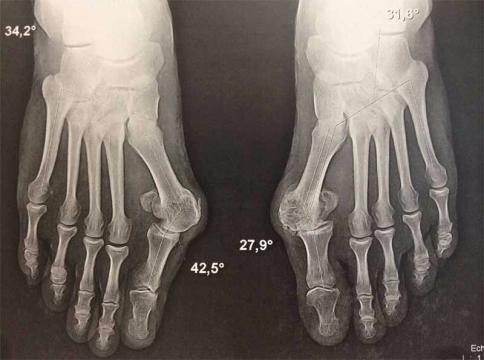

L’hallux rigidus est une arthrose du gros orteil du pied.

Cette arthrose du gros orteil entraînant une raideur de l’orteil et des douleurs. Parfois associé à une déformation en hallux valgus, l’hallux rigidus peut provoquer une boiterie avec appui sur la face latérale du pied.